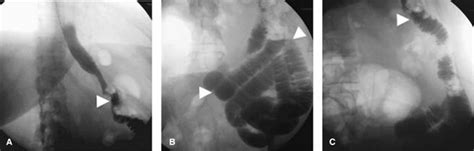

Figura 2: Anatomía Postquirúrgica de BPGYR

La anatomía postquirúrgica de la BPGYR en un paciente de 42 años, 24 horas después de la cirugía, muestra un adecuado paso del medio de contraste del esófago distal hacia el reservorio gástrico (aproximadamente 30 mL). No se evidencia fuga ni comunicación anómala. Tampoco hay signos de fugas o estenosis en la anastomosis gastroyeyunal. Se observa tránsito normal del medio hidrosoluble a través del asa alimentaria y opacificación completa del intestino delgado distal.

Figura 3: Anatomía Postquirúrgica de la GVM

La anatomía postquirúrgica de la GVM en un paciente masculino de 51 años, 24 horas después del procedimiento, revela un paso adecuado del medio de contraste hidrosoluble a través de la unión esofagogástrica. El estómago se presenta tubular, largo y delgado, sin evidencia de fugas o torsión. Se observa un vaciamiento gástrico normal y paso del contraste hacia el duodeno e intestino delgado.

Figura 4: Anatomía Postquirúrgica de BPGUA

La anatomía postquirúrgica de la BPGUA en una mujer de 38 años, 24 horas después de la cirugía, muestra el paso adecuado del medio de contraste hidrosoluble del esófago distal al reservorio gástrico. No se observa dilatación del reservorio ni fugas en el sitio de la anastomosis. Se aprecia la opacificación del asa eferente y aferente; esta última es esperada por reflujo retrógrado y normalmente desaparece con las ondas peristálticas.